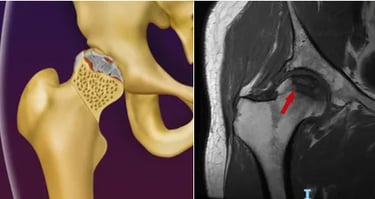

Osteonecrose da cabeça do fêmur

A Osteonecrose da cabeça do fêmur ocorre devido a um defeito na circulação sanguínea para a cabeça do fêmur, levando à morte do osso nessa região, fazendo com que o paciente tenha dor no quadril, muitas vezes acompanhada de dor na coxa.

Essa dor é pior aos movimentos ou ao fazer esforços físicos, muitas vezes limitando o paciente de andar médias distâncias.

Faz-se o diagnóstico com a Ressonância Magnética.

Em relação ao tratamento, não existe uma medicação específica para tal patologia. Casos iniciais, ou seja, em que a esfericidade da cabeça femoral está preservada, o tratamento é feito com uma cirurgia chamada de descompressão ou foragem, na qual remove-se o osso necrótico com uma broca, seguida da colocação de enxerto no local, para estimular a formação de osso normal.

Faz-se o tratamento com a prótese de quadril em casos avançados, ou seja, em que houve colapso/retificação da cabeça femoral ou quando já existe artrose instalada.